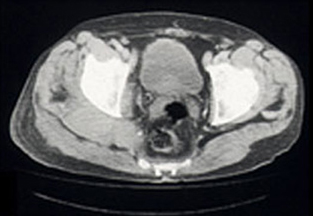

Radiography of his hips, pelvis and lumbosacral spine revealed mild degenerative changes only. A bone scan showed increased uptake in the region of the right buttock, right sacroiliac joint and the superior aspect of the right acetabulum. Computed tomography (CT) scan revealed diffuse swelling involving the right gluteus medius and piriformis muscles (Box, Figure 1). Magnetic resonance imaging (Box, Figure 2) confirmed these findings, but also showed swelling of the obturator internus and part of the gluteus maximus muscles, as well as some increased signal in the right iliac bone seen on T1-weighted images.